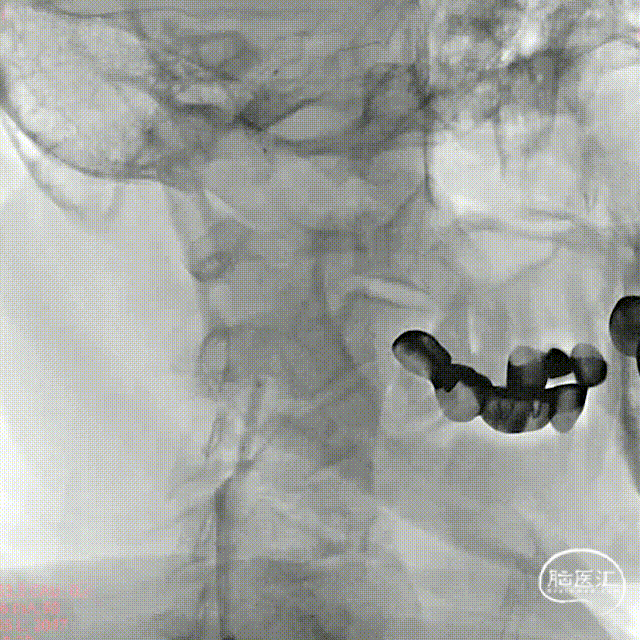

应用Seldinger技术穿刺成功后,置入6F动脉鞘。经导管鞘送入6F指引导管,5F MPA1引导下送至右侧颈总动脉,造影示右侧颈内动脉C1段局限性重度狭窄,狭窄率约95%,前向血流减慢,右侧大脑中动脉显影可,血流速度正常,远端灌注减弱。

选取合适工作角度,路图引导下使用0.014inch 200cm 微导丝超选越过狭窄病变段至右侧颈内动脉海绵窦段,随后沿微导丝将Safecer栓塞保护器输送至颈内动脉C1段并进行释放,Safecer栓塞保护器输送鞘中间层为不锈钢扁丝线圈推送顺畅释放;伞体由镍钛合金进行对称编织,释放后伞体可顺应血管,与血管壁完美贴合。

选用2.5mm*15mm球囊扩张导管对狭窄部进行预扩张,造影显示扩张效果欠佳,再次使用4mm*30mm球囊扩张导管对狭窄部进行扩张,造影显示扩张效果良好。

后再释放SEPX 10-7-40-135支架,释放后管腔扩张较前好转,造影可见支架位置满意,管腔扩张良好,颈内动脉血流较前增高,颅内灌注较前好转。

术后造影显示颈内动脉狭窄处管腔重塑良好,前向血流明显,颅内灌注较前改善。